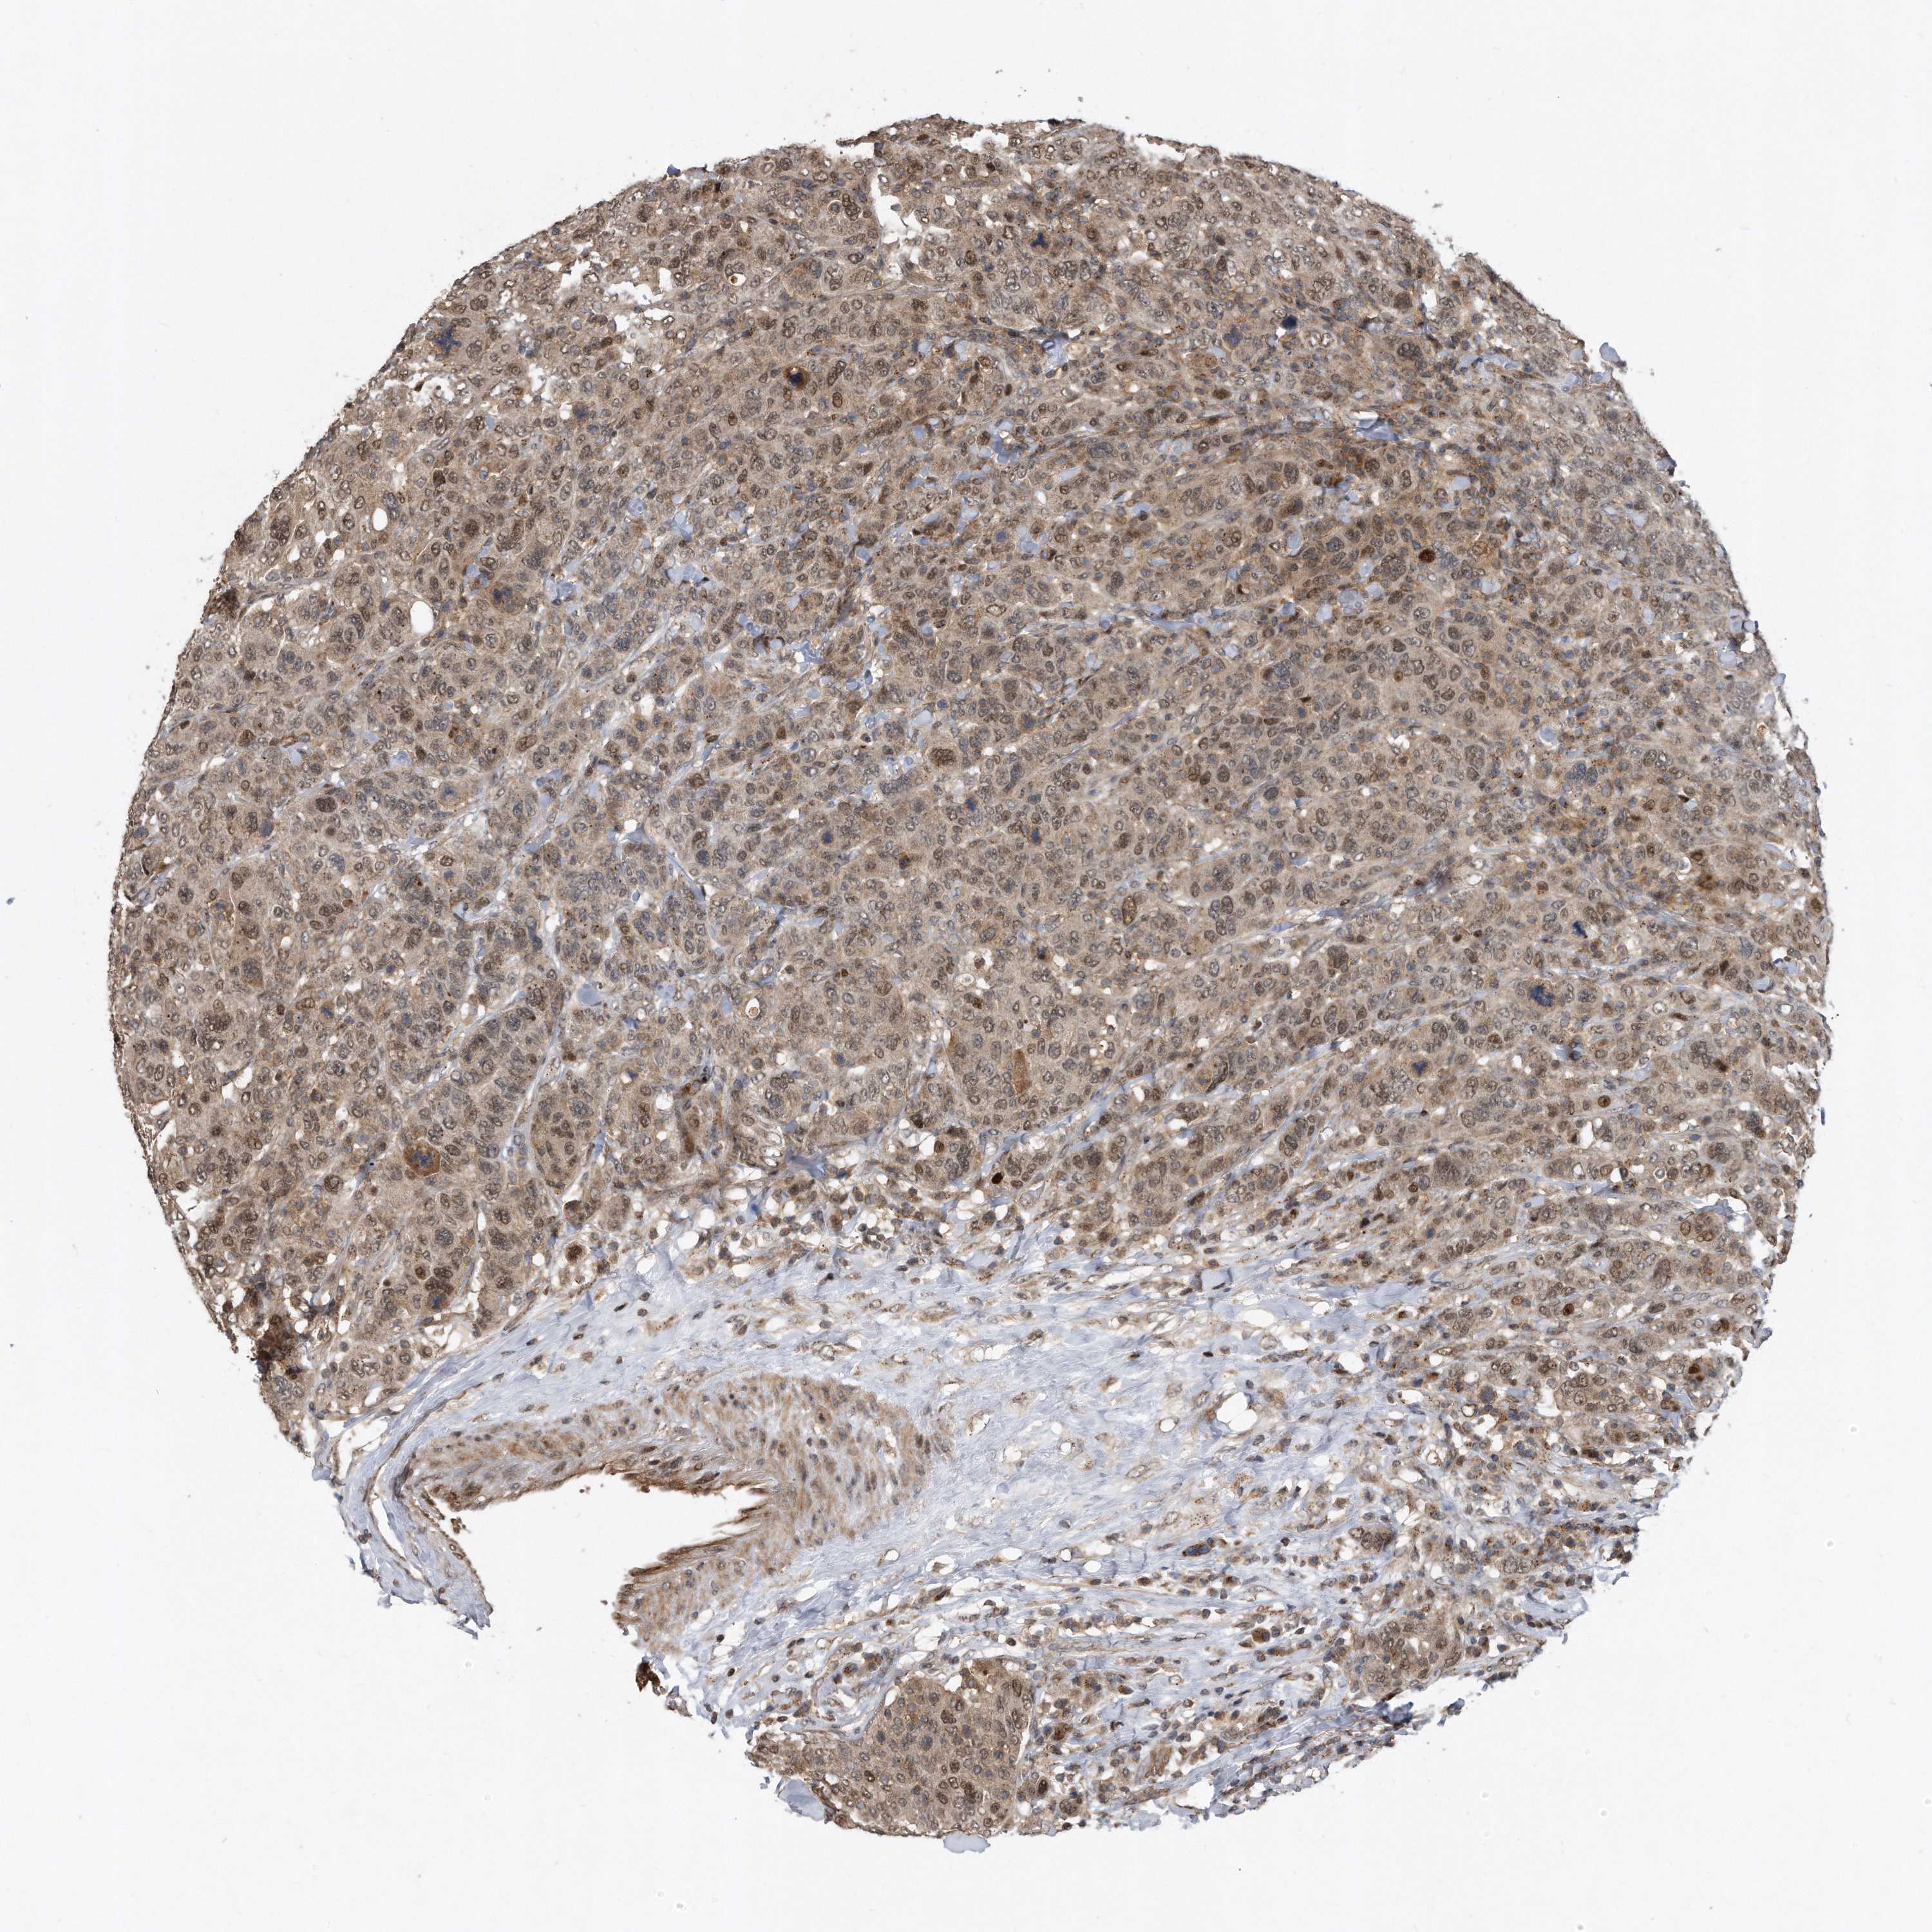

CANCER BREAST CANCER Show tissue menu

BRCA TCGA BRCA VALIDATION PROTEIN EXPRESSION